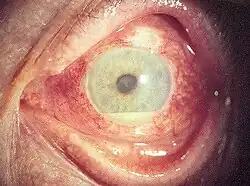

| Hypopyon seen as yellowish exudate in lower part of anterior chamber of eye | |

Hypopyon is a medical condition involving inflammatory cells in the anterior chamber of the eye.

It is an exudate rich in white blood cells, seen in the anterior chamber, usually accompanied by redness of the conjunctiva and the underlying episclera. It is a sign of inflammation of the anterior uvea and iris, i.e. iritis, which is a form of anterior uveitis. The exudate settles at the dependent aspect of the eye due to gravity. It can be sterile (in bacterial corneal ulcer) or not sterile (fungal corneal ulcer).